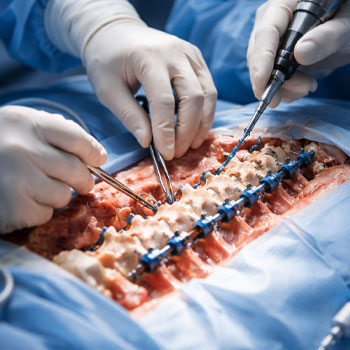

What orthopedic services are available?

We provide advanced orthopedic care including joint pain treatment, fracture management, arthritis care, and minimally invasive procedures with expert specialists at Jayabhrathi Multi Specialty Hospital